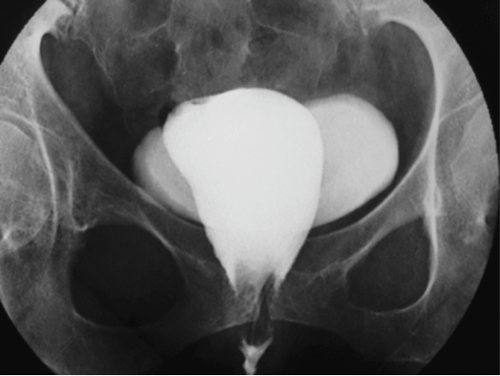

A 35-year-old female patient attended for investigations.

1. What investigation has been performed?

2. Describe the findings.

3. What is the diagnosis?

4. What treatment is usually required?

- A cystogram has been performed.

- Contrast is seen to opacify the urinary bladder as well as another structure which has a more longitudinal appearance on the image.

- The diagnosis is a vesicovaginal fistula (VVF). In developing countries, the commonest cause is prolonged labour, but in developed countries 90% are seen due to bladder injury following pelvic surgery. Risk factors include previous surgery, diabetes, endometriosis and infection. Patients usually present with leakage of urine into the vagina, causing urinary incontinence.

- Conservative management can occasionally be successful if a VVF is diagnosed within the first few days of surgery and a urinary catheter is left in situ. Alternatively, surgical repair may be necessary, particularly if the VVF is longstanding.